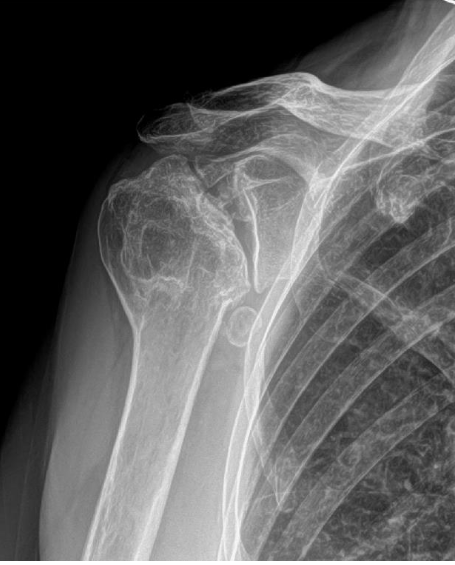

If your shoulder joints and the surrounding tissues are seriously damaged, you may need surgery to replace it. The most common reason for shoulder replacement surgery is pain that has not responded well to conservative management. Conditions that may cause damage to the shoulder joint include:

- Fractures: Fracture of the humerus or the upper arm bone.

- Osteoarthritis: A form of arthritis caused by wear and tear, damaging the cartilage covering the ends of the shoulder joint, allowing for smooth movement.

- Rheumatoid arthritis: An autoimmune and inflammatory condition which damages the cartilage and the underlying bones of the shoulder joint.

- Osteonecrosis: Disruption of blood flow to the humerus, causing the shoulder joint to breakdown.